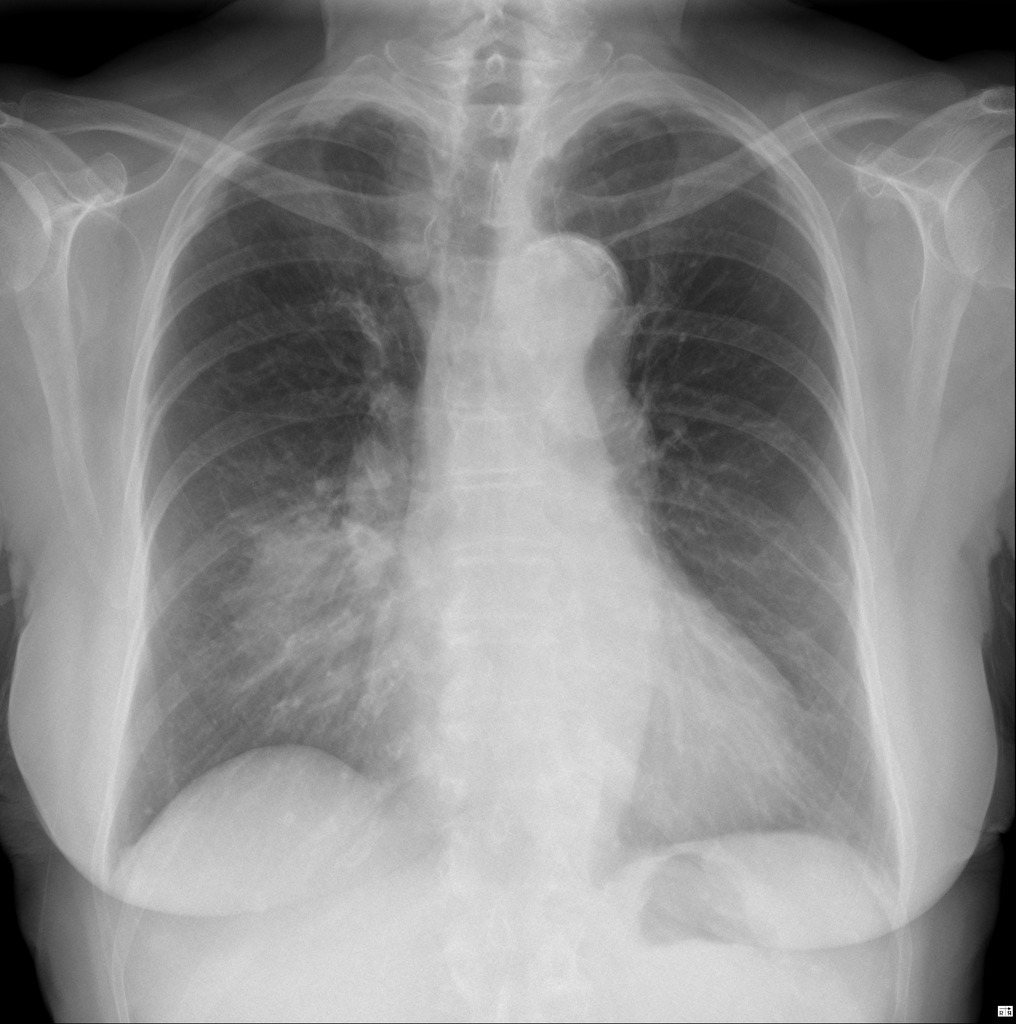

How to approach a CXR

ABCDE

Airway - trachea, carina + bronchi, hilar structures

Breathing - lungs, pleura

Cardiac - heart size, borders

Diaphragm - costophrenic angles

Everything else - mediastinal contours, bones, soft tissue, tubes/ valves/ pacemakers

Review areas - lung apices, retrocardiac, behind diaphragm, peripheral lungs, hilar